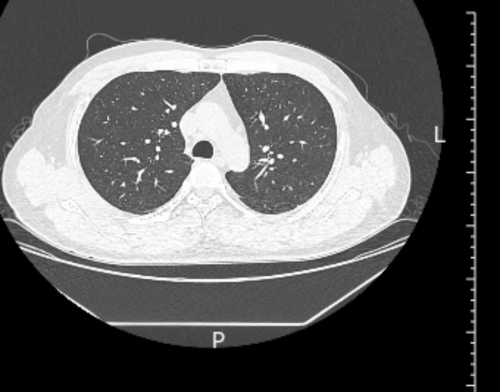

2025年3月28日,38岁俞某因重症新冠肺炎在哈尔滨大学第四附属医院感染科住院,检查结果显示:大白肺,且艾滋病晚期,CD3+CD4+低于26(一般低于50便是艾滋病晚期)呼吸困难。

图1 俞某2025年3月26日CT片重症间质性肺炎(大白肺)